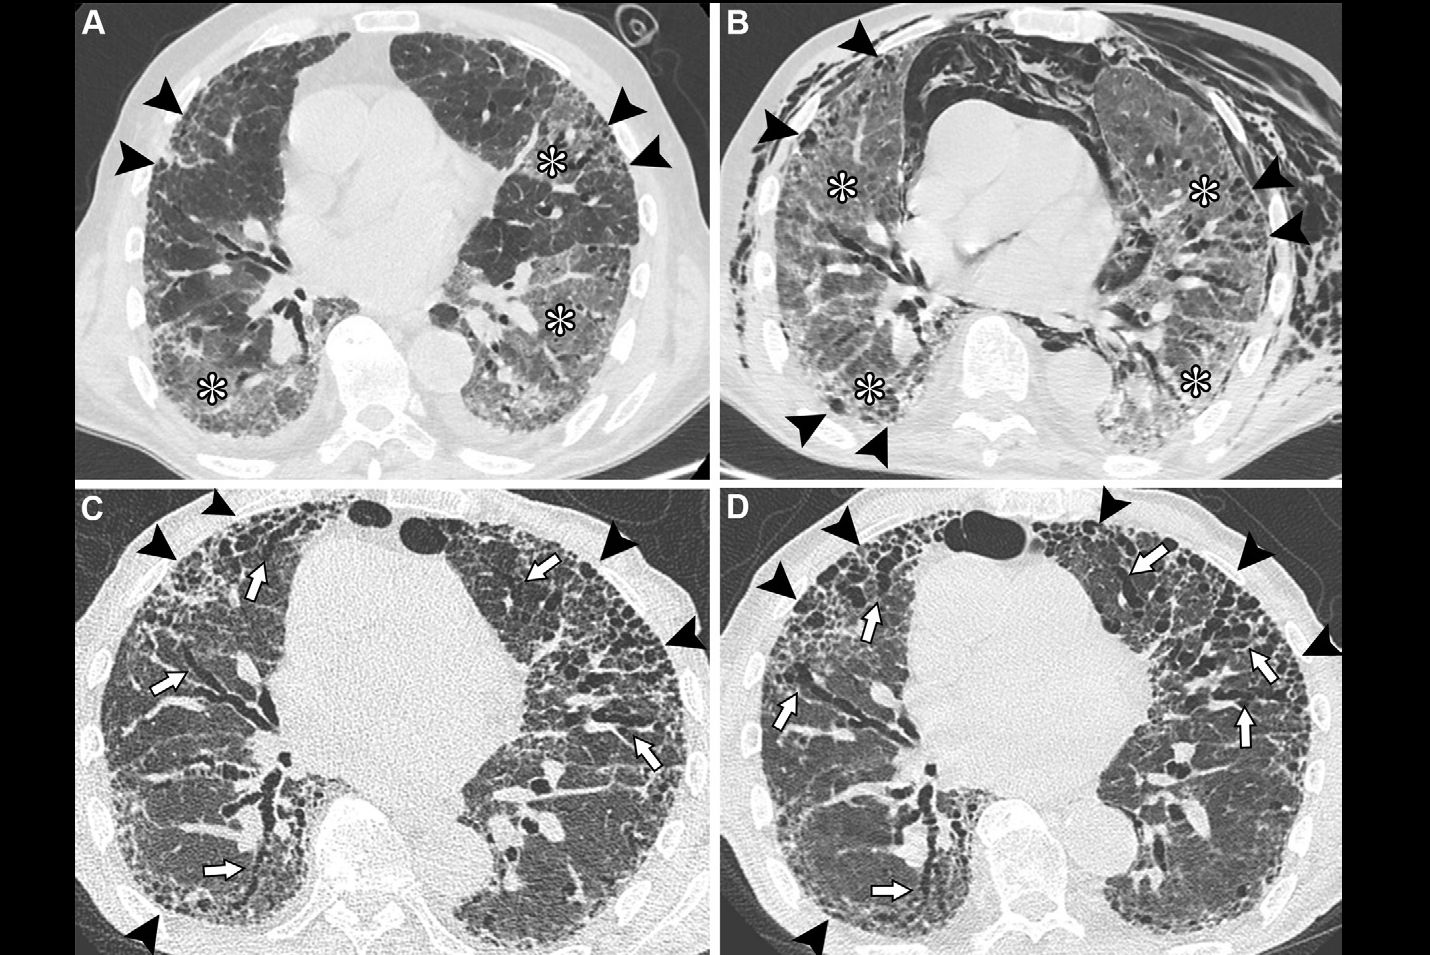

A new study published today in Radiology is bolstering the argument for CT lung screening by determining that cancers detected on screening scans are very similar to the ones diagnosed outside of the screening setting.

CT lung screening has received renewed interest following the publication of results in 2010 indicating that screening could reduce mortality by more than 20% in a population of current and former smokers. But one argument being used against the implementation of broad-based CT screening is that it might detect slow-growing cancers that might never pose a threat to individuals; working up these cancers would be expensive and could cause patient morbidity, the argument goes.

Today's results may allay those concerns, according to an article in our CT Digital Community. In the study, a group led by Dr. Claudia Henschke analyzed the characteristics and progression of screen-detected cancers and compared them to lesions found under normal clinical conditions. The result: there wasn't much difference between the two.